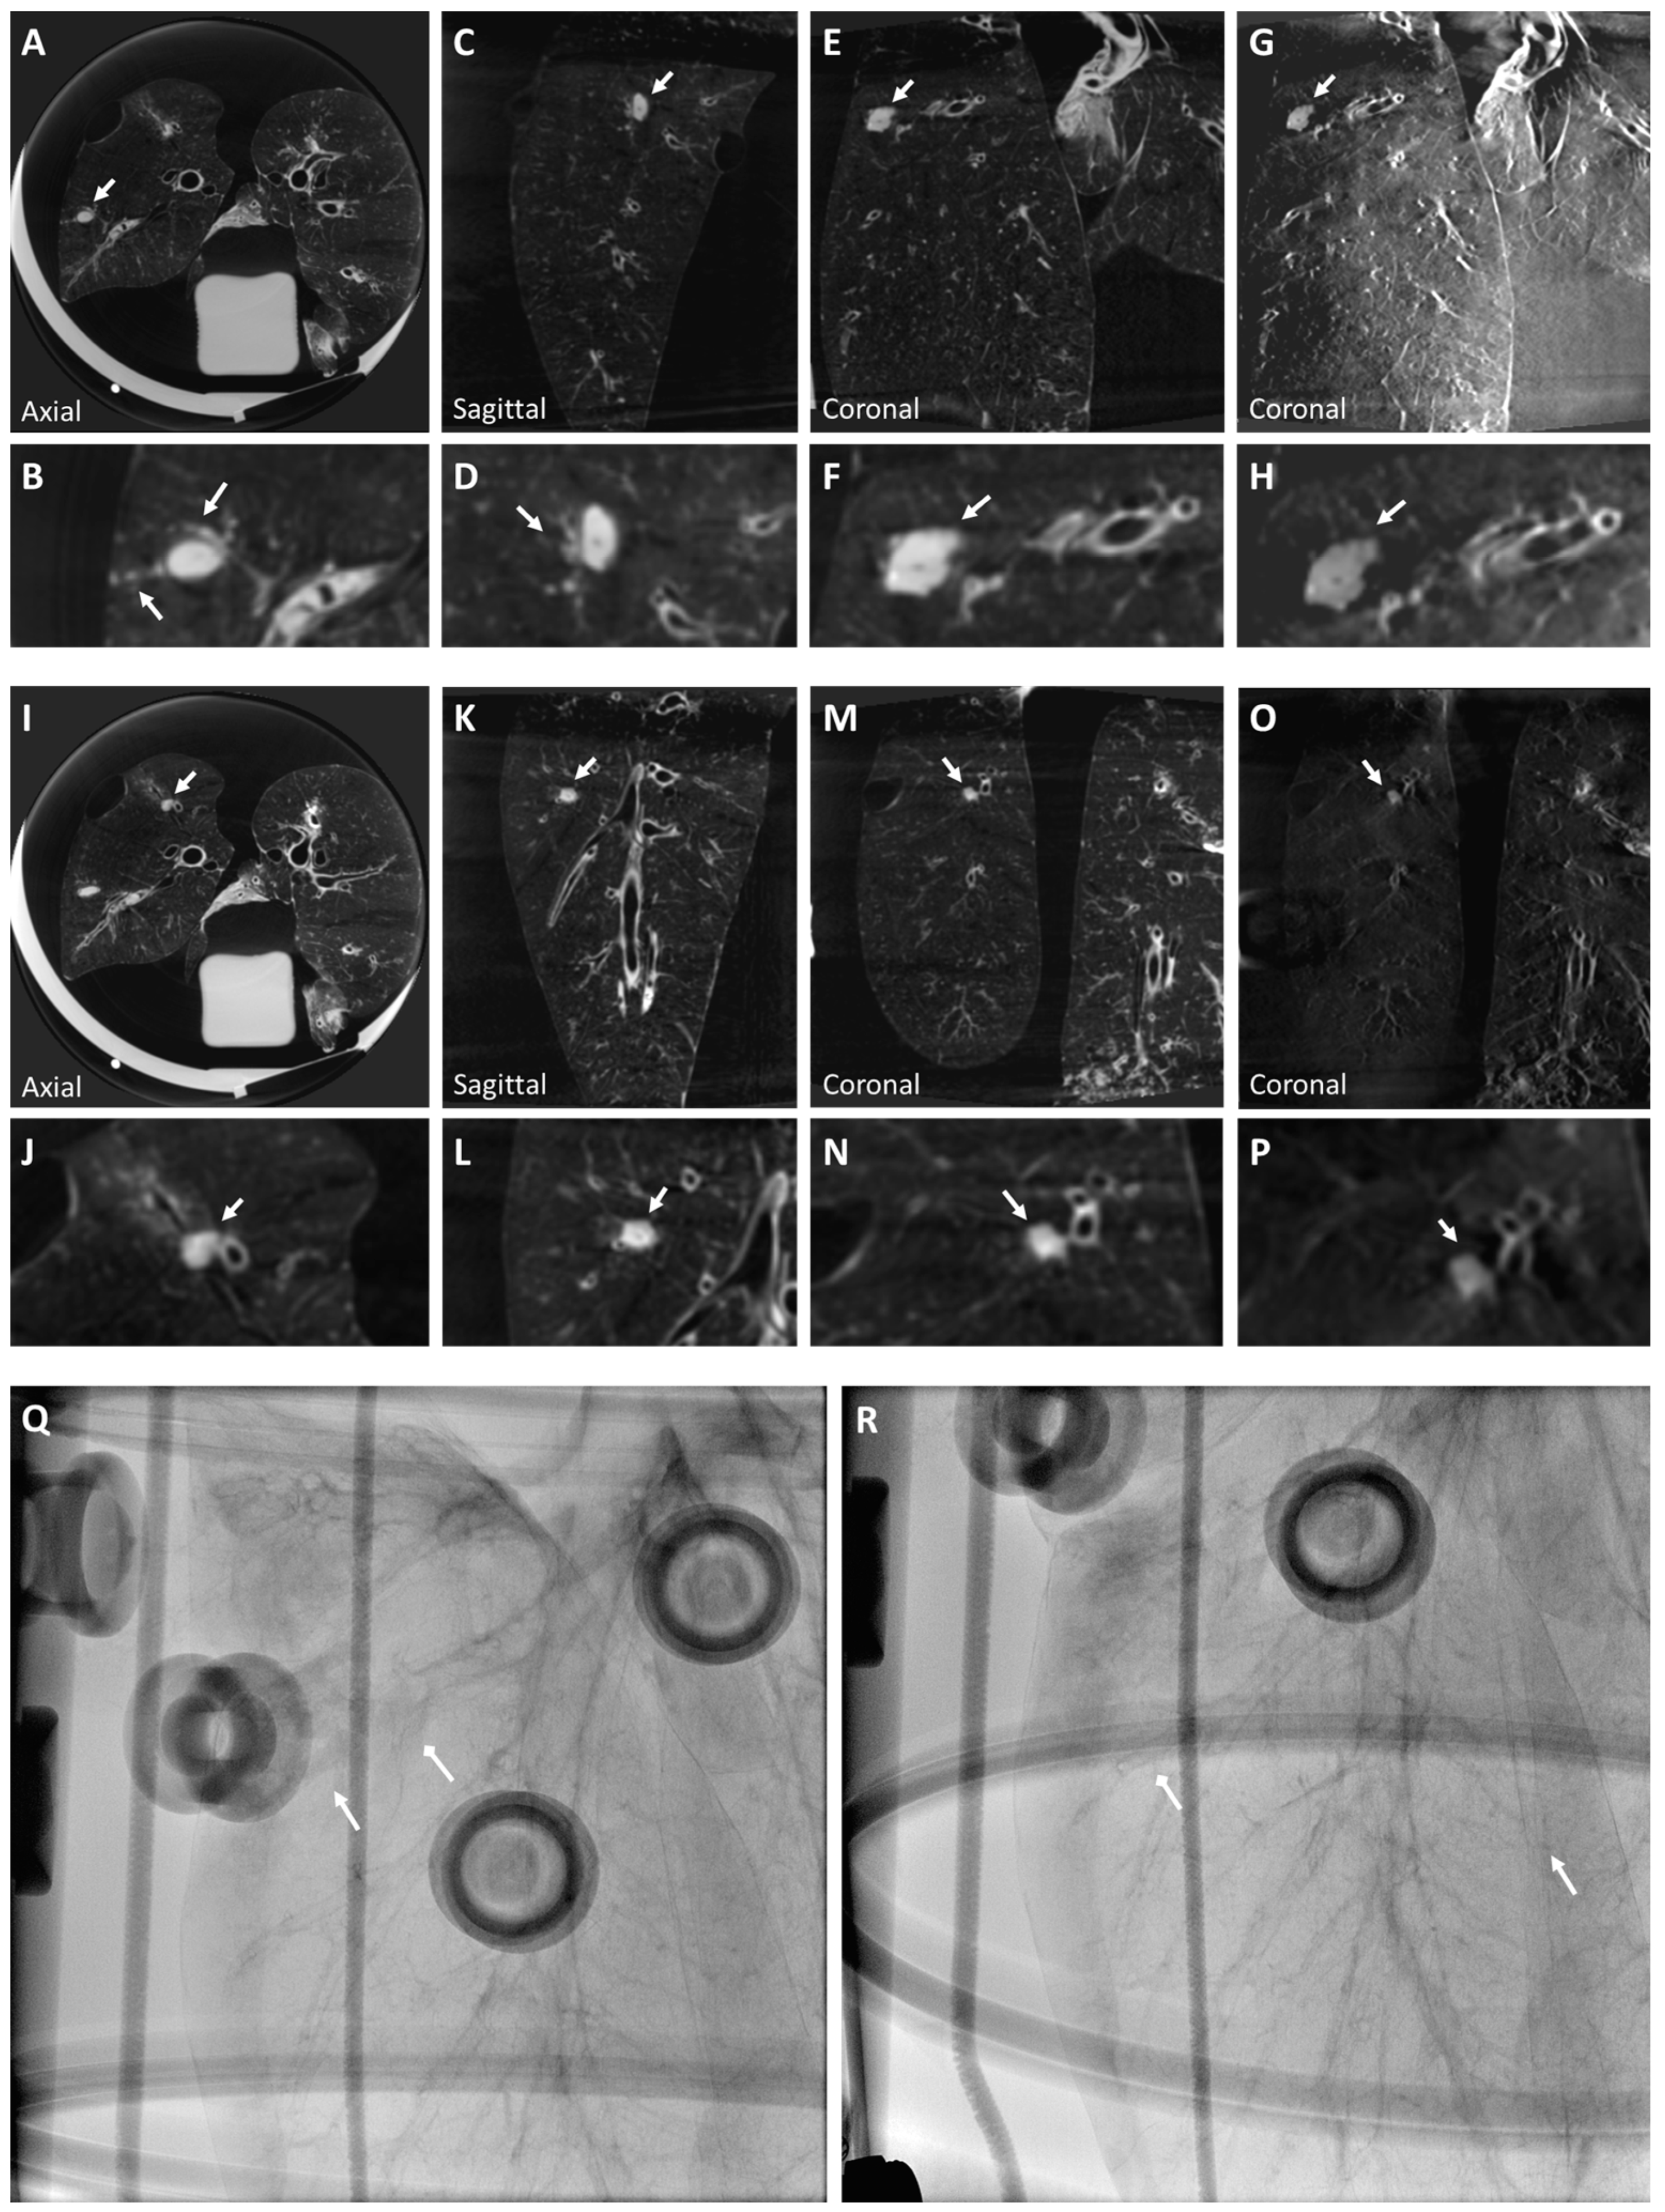

3.1. Ex Vivo Swine Lungs